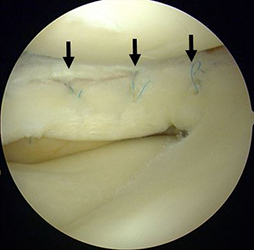

半月は、膝関節の大腿骨と脛骨の間にあるC型をした軟骨様の板で内側・外側にそれぞれがあり、クッションとスタビライザーの役割をはたしています。半月板損傷は、スポーツ外傷や加齢性の変化などにより、幅広い年齢層に生じます。症状は、引っかかり感や関節が曲がらない・伸びないなどの関節可動域制限、しゃがんだ際などの痛みであり、痛みがひどい場合には、夜間寝返りで目が覚めることもあります。半月板は損傷すると治りにくい組織です。保存的治療で症状改善が得られない場合、関節鏡視下の半月板部分切除術や縫合術をお勧めします。

関節鏡視下半月板部分切除術・縫合術

前方に逸脱した外側半月板を整復し縫合した。